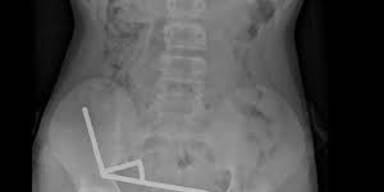

Die Magneten, die in Neuseeland seit Anfang 2013 verboten seien, seien auf der Temu-Plattform gekauft worden, teilten die Ärzte mit. Eine Röntgenaufnahme habe gezeigt, dass die Magneten sich in verschiedenen Bereichen des Darms aufgrund der Anziehungskraft zu vier geraden Linien zusammenklumpten. Den Ärzten zufolge starb durch die Kraft der Magneten an vier Stellen im Dünn- und Dickdarm Gewebe ab.